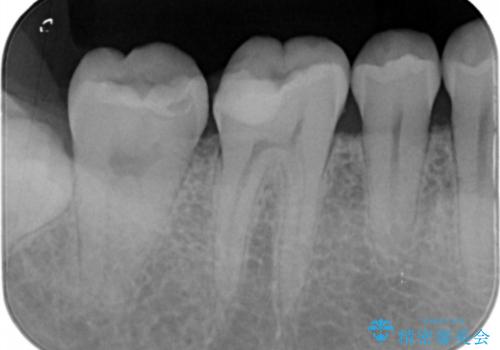

- 右下6・7番の治療のやり変えを主訴に来院された患者様です。

保険の材料が劣化し中で虫歯が進行しているため、古い材料と虫歯を全て除去した上で詰め直す必要がありました。

切削量・形態を考慮し、セラミックインレーでの治療を計画しました。